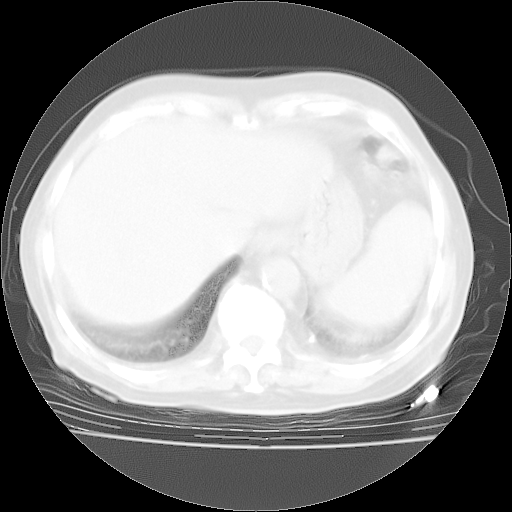

4月28日肺部CT——再次出现类似去年5月9日——透光度降低,“间质性”改变。

个人阅读4.14日肺部CT平扫:纵隔窗无异常,但肺窗示:双下肺内、后基底段有片絮状侵润影,部位以后基底段为著,以间质改变为主,呈急性肺泡炎征像,和首次住院影像学有相似之处。仅是个人读片,明日请相关专家再读片哈。其它建议同上。